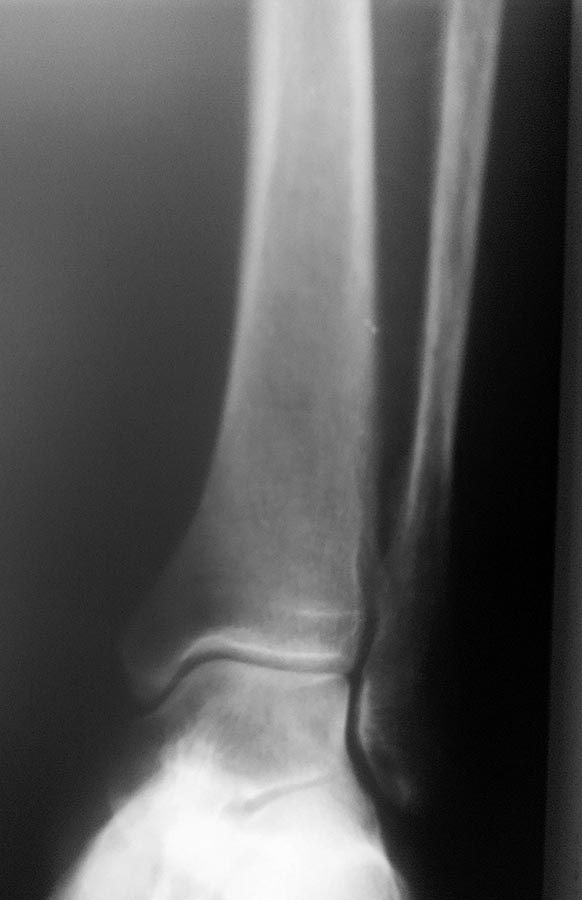

[Ortho] Оперировать или нет.

С нагрузкой весом.